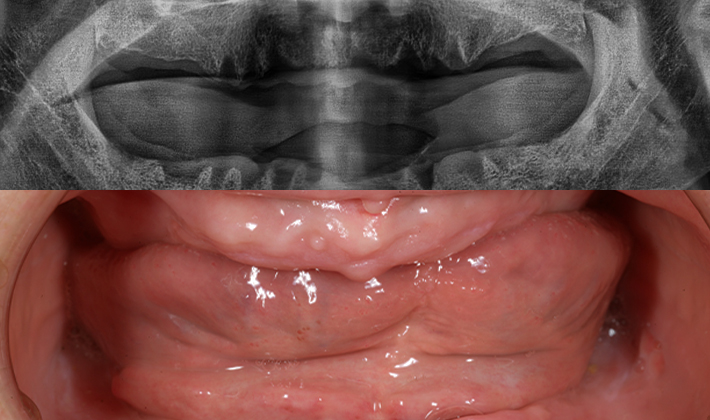

5060 시니어 임플란트

건강하고 오래가는 시니어 임플란트,

치료 사례부터 남다릅니다.

before

after

※ 위 임상사진은 동일조건으로 촬영되었으며, 사진에 대한 별도의 조작이 처리되지 않았습니다.

※ 위 임상사진 및 포트레이트는 환자와의 포괄적인 초상권 계약 이후 사용하고 있습니다.

※ 수술 및 치료과정에서 부작용이 발생할 수 있으므로 충분한 상담과 신중한 판단이 요구됩니다.

실제 치료 사례

수많은 환자들이 고민 끝에 선택한 치료,

그리고 그 후의 놀라운 변화

- ※ 위 임상사진은 365서울원탑치과에서 진료를 시작하고 마친 동일한 환자의 사진입니다.

- ※ 위 임상사진은 동일한 장소에서 동일한 조건으로 촬영되었으며, 사진에 대한 별도의 조작이 처리되지 않았습니다.

- ※ 수술 및 치료 과정에서 부작용이 발생할 수 있으므로 의료진과의 충분한 상담과 신중한 판단이 요구됩니다.